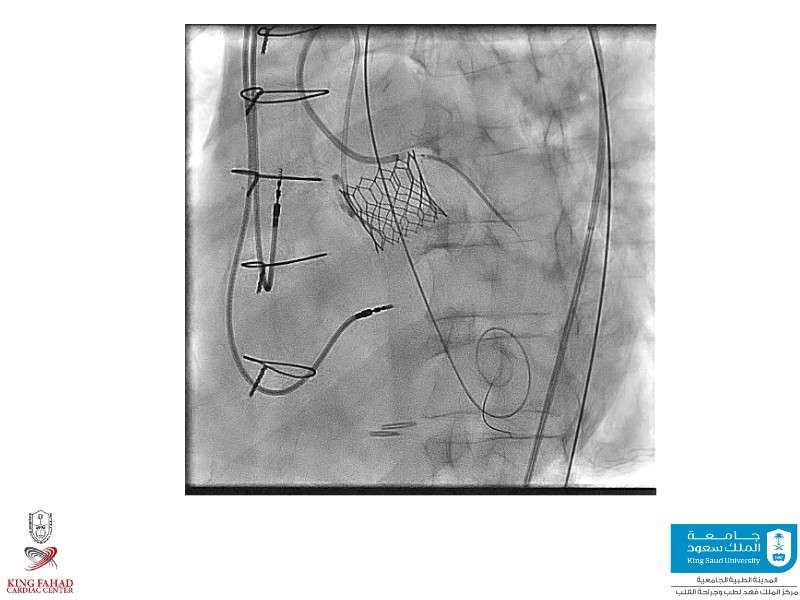

This session helps you anticipate and address complex scenarios such as mitral valve-in-valve, TAV-in-SAV, and valve-in-valve-in-valve procedures. Learn from expert case discussions that explore procedural strategies, technical challenges, and best practices to optimize outcomes in redo structural heart interventions.